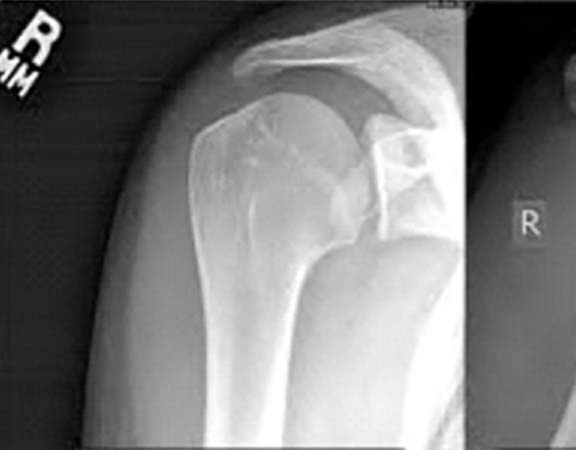

FRATURAS DO OMBRO

As fraturas do úmero proximal acontecem basicamente em 2 perfis de paciente: em jovens após acidente de alta energia, principalmente queda de moto, e outra, no paciente acima de 50 anos, que simplesmente caem, frequentemente relacionada ao osso com osteoporose. Dor no ombro, impossibilidade de mexer e hematoma. Este último pode se espalhar pelo peito e braço Após a avaliação médica, no serviço de emergência, exame de raio-X será solicitado. Algumas vezes a tomografia computadorizada esclarece detalhes quando a fratura é complexa. Ressonância magnética é solicitada nos casos em que a suspeita de fratura é grande, porém o exame radiológico é normal. São os casos de fraturas ocultas. O tratamento para a maior parte dessas fraturas é com tipóia. Repouso do membro acometido por aproximadamente 45 dias é suficiente para a consolidação do osso. A cirurgia é realizada para aqueles pacientes que apresentam grande desalinhamento dos fragmentos da fratura, fraturas dentro da articulação e fraturas com luxações. O principal meio de fixação é com placa e parafusos. Algumas vezes, dependendo do tipo de fratura e idade do paciente, é necessário substituir a região fraturada por uma prótese.